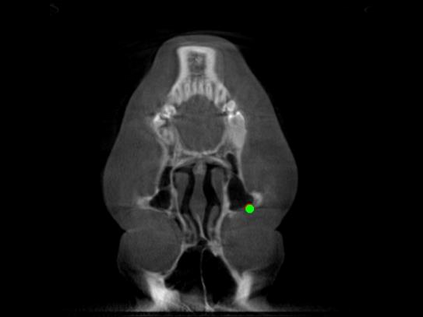

Detecting 3D landmarks on cone-beam computed tomography (CBCT) is crucial to assessing and quantifying the anatomical abnormalities in 3D cephalometric analysis. However, the current methods are time-consuming and suffer from large biases in landmark localization, leading to unreliable diagnosis results. In this work, we propose a novel Structure-Aware Long Short-Term Memory framework (SA-LSTM) for efficient and accurate 3D landmark detection. To reduce the computational burden, SA-LSTM is designed in two stages. It first locates the coarse landmarks via heatmap regression on a down-sampled CBCT volume and then progressively refines landmarks by attentive offset regression using multi-resolution cropped patches. To boost accuracy, SA-LSTM captures global-local dependence among the cropping patches via self-attention. Specifically, a novel graph attention module implicitly encodes the landmark's global structure to rationalize the predicted position. Moreover, a novel attention-gated module recursively filters irrelevant local features and maintains high-confident local predictions for aggregating the final result. Experiments conducted on an in-house dataset and a public dataset show that our method outperforms state-of-the-art methods, achieving 1.64 mm and 2.37 mm average errors, respectively. Furthermore, our method is very efficient, taking only 0.5 seconds for inferring the whole CBCT volume of resolution 768$\times$768$\times$576.